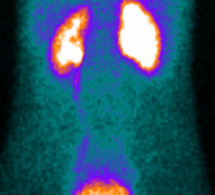

-Diagnostic étiologique d'une hyperthyroïdie -Surveillance des nodules ne relevant pas d'une chirurgie d'emblée -Diagnostic étiologique des hypothyroïdies congénitales -Identification du tissu...